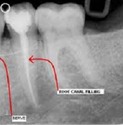

• Root Canals - Incisors, Canines and Bicuspids